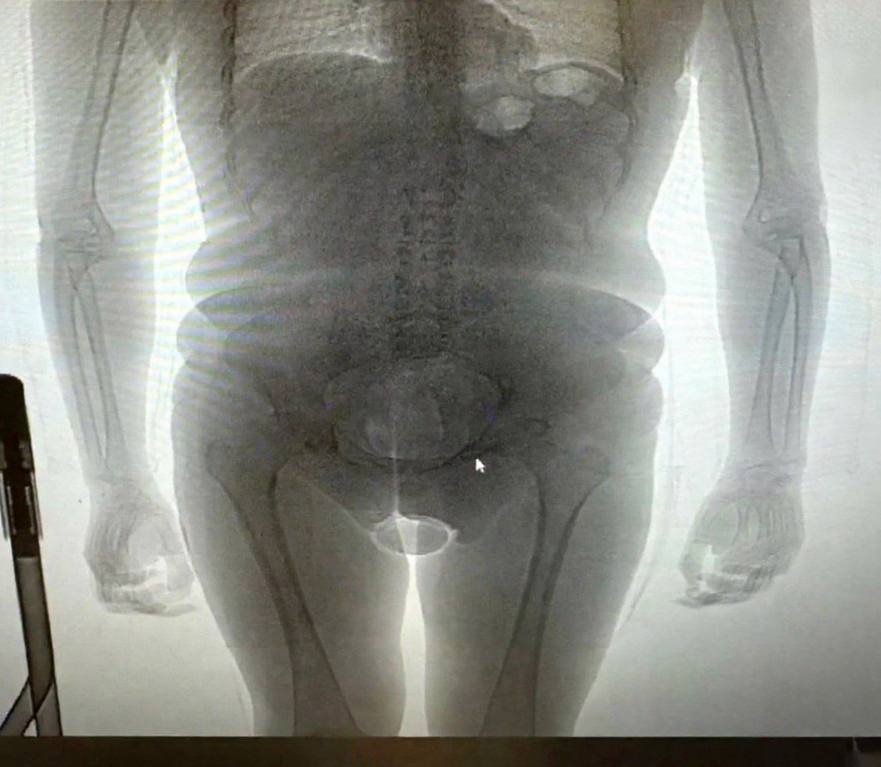

В аэропорту Домодедово задержали бразильского трансгендера который пытался тайком провезти наркотики в презервативах Таможенники обратили внимание на подозрительную девушку прилетевшую из Дубая При проверке на рентгене у туристки нашли два презерватива с кокаином Один она прятала в нижнем белье а второй в своем теле Иностранку арестовали против нее возбудили уголовное дело о контрабанде наркотиков Движение ЛГБТ признано экстремистским и запрещено в России Подписаться на РЕН ТВ МАХ Отправить новость

Трансгендер пытался провезти в Россию наркотики внутри своего тела В 22 летняя гражданка Бразилии прилетела в Домодедово из Дубая Она сразу показалась таможенникам подозрительной Во время досмотра в нижнем белье у девушки нашли презерватив с белым порошком Еще один такой оказался в прямой кишке Пассажирка призналась что это кокаин который она везла по заказу некоего мужчины А еще выяснилось что в прошлом она была мужчиной Иностранку арестовали против нее возбудили уголовное дело о контрабанде наркотиков Читайте Газету Ru в MAX Участвуйте в розыгрыше